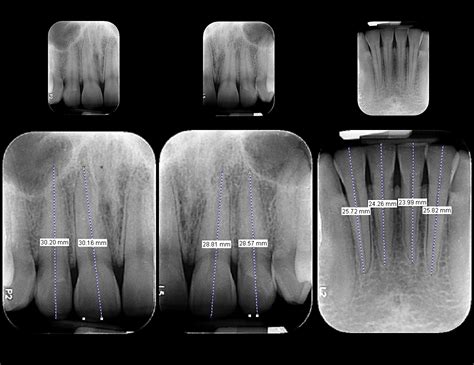

La radiografía periapical es una técnica de imagen que permite visualizar en detalle toda la estructura de uno o varios dientes, incluyendo la corona, la raíz y el hueso que los sostiene. Gracias a esta visión completa, se convierte en una herramienta fundamental para detectar patologías que no se observan fácilmente a simple vista, como infecciones profundas, alteraciones en el hueso o daños en la raíz del diente.

- Análisis de Raíces Dentales: Otro de los usos más frecuentes es analizar la forma, tamaño y posición de las raíces dentales.

Para que la radiografía periapical cumpla su función diagnóstica con la máxima precisión, es importante seguir una técnica adecuada durante su realización. Existen dos métodos principales para obtener esta imagen: la técnica paralela y la técnica de la bisectriz.

- Técnica Paralela: La técnica paralela es la más precisa y se utiliza siempre que sea posible. En ella, el sensor se coloca paralelo al diente y el haz de rayos X se dirige de forma perpendicular.